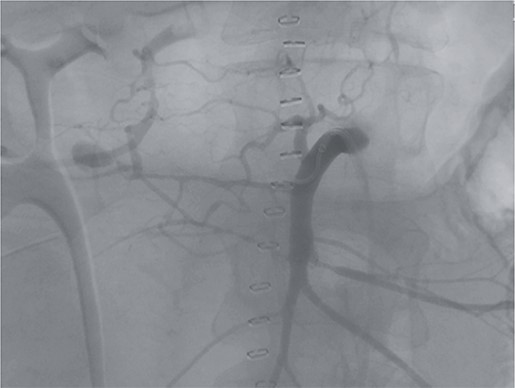

Postoperatively, the patient achieved hemodynamic stabilization in the intensive care unit. On the sixth postoperative day, there was a recurrence of circulatory collapse in addition to relevant bloody discharge through the drains. CT imaging once again revealed an active bleeding of the pancreaticoduodenal artery, which was successfully treated interventionally using coiling (Figs 2 and 3).

Angiography revealing the aneurysm of the pancreaticoduodenal arcade.

Postinterventional angiography, showing the aneurysm of the pancreaticoduodenal arcade, after interventional coiling.